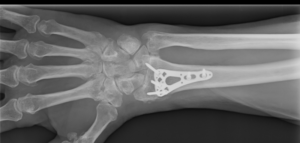

Also called radiographs, X-rays are one of the most common imaging tools used to look at internal body structures. They are often the first test ordered by physicians to determine the cause of pain or swelling and help rule out broken bones. X-rays use electromagnetic radiation to create images of bones and other dense matter, while soft tissue remains dark. Orthopedic surgeons also use X-rays to determine if a broken bone will require surgery or can heal without surgery in a cast or brace.